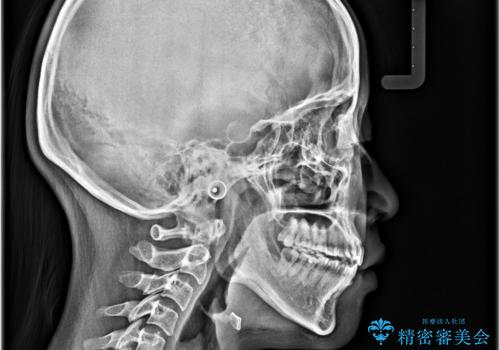

- 前歯の開咬を気にして来院された患者様です。

開咬の治療は、前歯を閉じるように動かすとともに、上下臼歯を圧下(骨内にめり込ませる)させることで進めて行きます。

インビザラインは臼歯の圧下を効果的に行えるため、インビザラインを用いて矯正治療を行うこととしました。